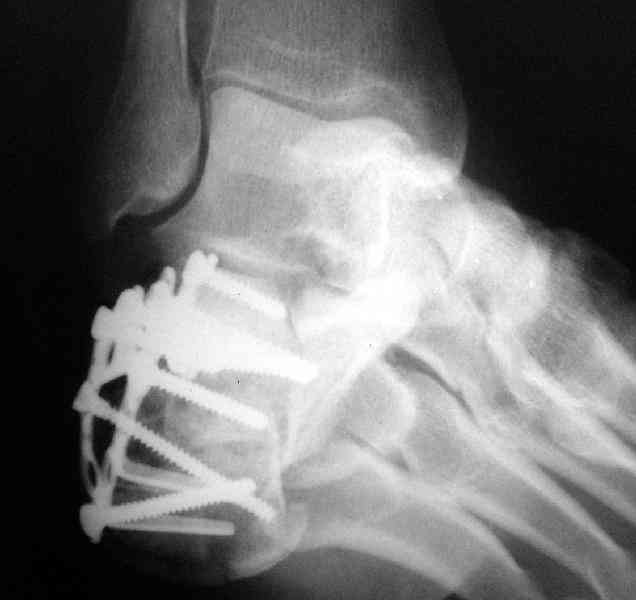

Пяточной пластиной

Открытый и закрытый способы лечения.

MOST OF MY COLLEGUES WOULD OPEN IT LATERALLY( a flap) and having a proper reduction would put a plate.